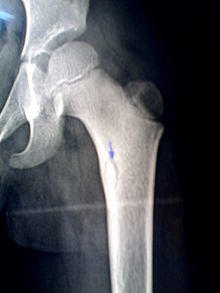

A sequestrum (plural: sequestra) is a piece of dead bone that has become separated during the process of necrosis from normal or sound bone.

The sequestra are surrounded by sclerotic bone which is relatively avascular (without a blood supply). Within the bone itself, the haversian canals become blocked with scar tissue, and the bone becomes surrounded by thickened periosteum.

At the same time as this, new bone is forming (known as involucrum). Openings in this involucrum allow debris and exudates (including pus) to pass from the sequestrum via sinus tracts to the skin.